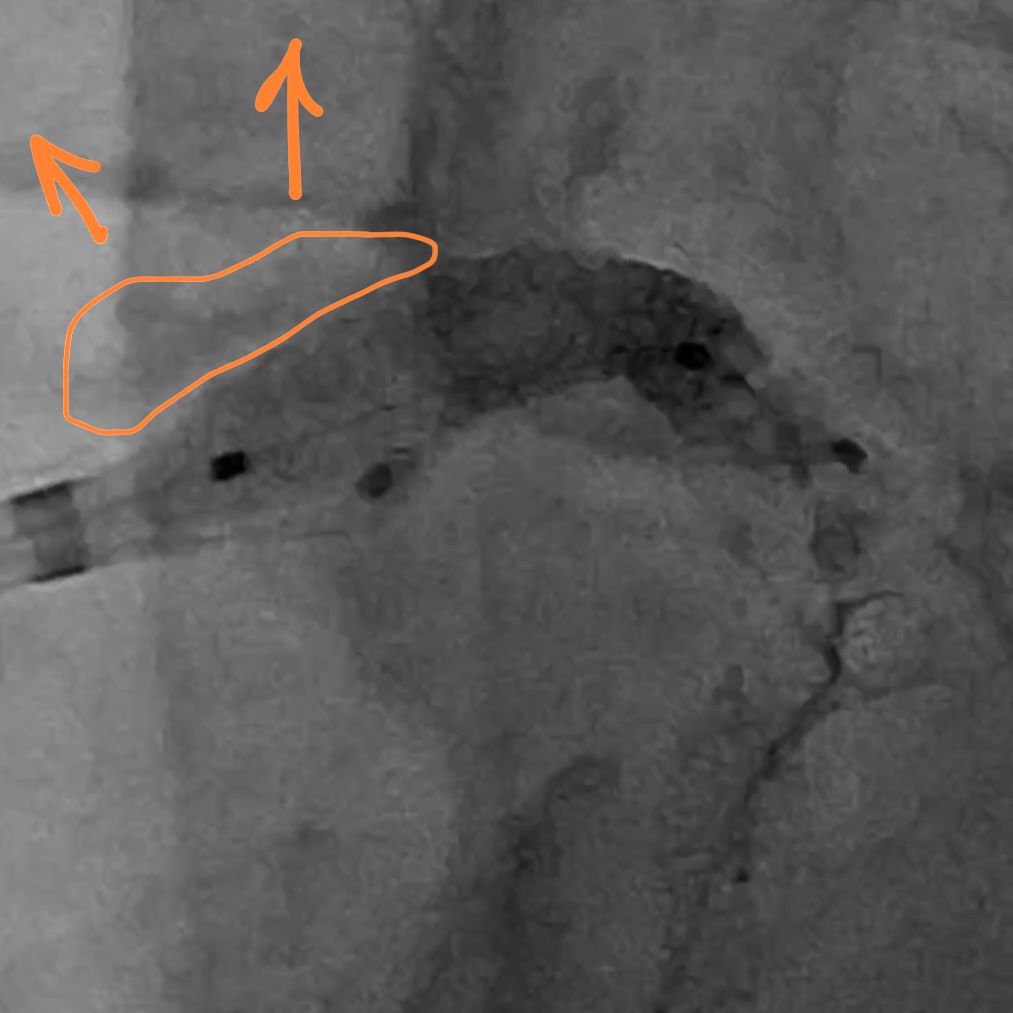

Here is the balloon inflation. Note the upward displacement of the nodules.